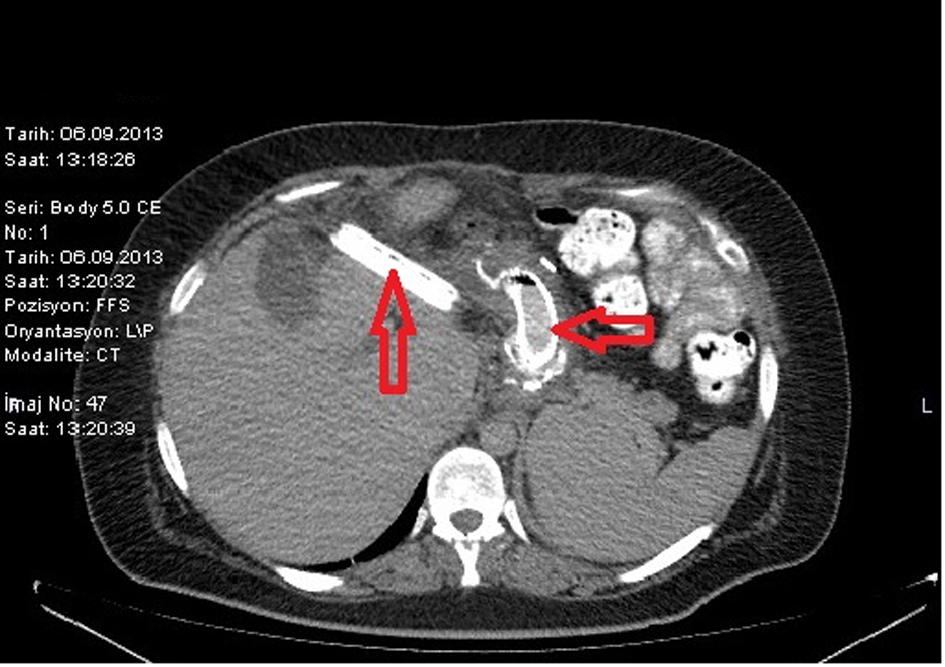

Endoscopic Biological Glue Injection for Treating Multiple StapleLine

Endoscopic Biological Glue Injection for Treating Multiple StapleLine Staple Line Leaks Following Sleeve Gastrectomy Leaks after laparoscopic sleeve gastrectomy (lsg) are not very frequent but are a difficult complication that can become chronic. Management of gastric leak after sleeve gastrectomy (sg) is challenging due to its unpredictable outcomes. Postoperative staple line leaks after sleeve gastrectomy, while rare, remain a potentially catastrophic complication. Benedix f, poranzke o, adolf d, et al. Do patients still benefit. Staple Line Leaks Following Sleeve Gastrectomy.